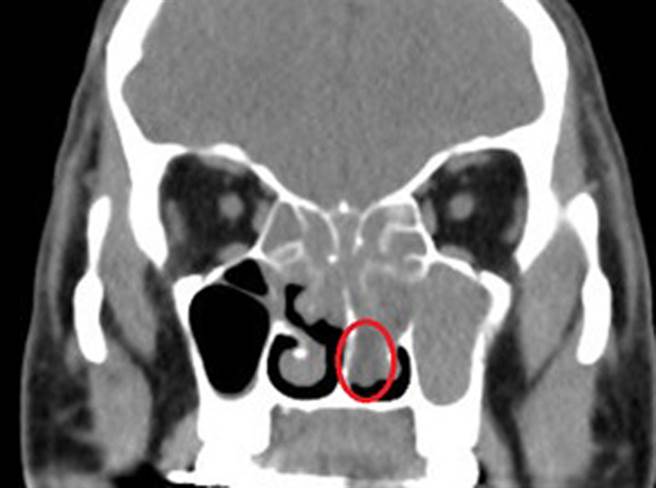

46岁吴姓男子长期鼻塞,几乎都靠嘴巴呼吸,也闻不到气味,求助屏东荣民总医院耳鼻喉科,经内视镜与电脑断层诊检查,发现他因慢性鼻窦炎导致鼻瘜肉增生阻塞,鼻瘜肉如一长串白葡萄塞满鼻腔,已长到下鼻道,马上安排手术,术后大幅改善。

张耿铭表示,若病患需要透过手术治疗,手术前会安排电脑断层诊断,需要拍摄的位置电脑断层不须打显影剂,不会有显影剂过敏与担心肾功能不好的问题。